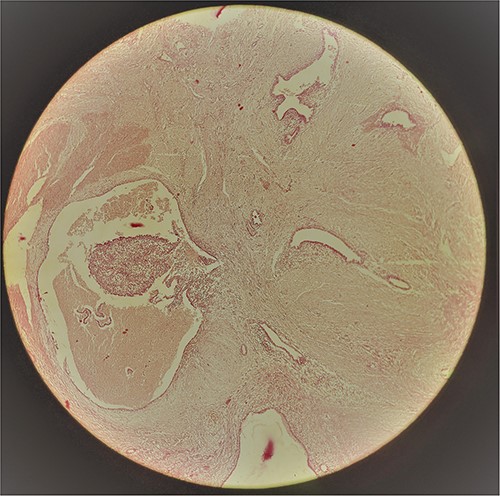

A 29-year-old female patient presented with a complaint of pain in lower abdomen for last 2 years. The pain would aggravate during menses. She also complained of a swelling at the site of her previous lower segment caesarean section (LSCS) scar for 1 year, which had gradually increased in size. She had underwent LSCS two and half years back. Nothing else was significant in history. Examination revealed a well circumscribed, firm mass at the surgical scar site, slightly to the right of the midline, ⁓6 cm × 5 cm in dimensions, fixed to underlying structures, especially on contraction of the rectus abdominis. Ultrasonography showed a heterogenous mass in the relation to the scar. Magnetic resonance imaging (MRI) revealed a well-defined heterogenous lesion extending into right rectus abdominus muscle, 4.2*3.1*2.2 cm in size with multiple thin septations within it, suggestive of scar endometriosis. Intraoperatively an irregular mass lesion was found in the subcutaneous scar tissue and was noted to be invading the rectus abdominis (Fig. 1). Enbloc excision of the endometrioma along with the involved portion of rectus sheath and rectus abdominis muscle was done (Figs 2 and 3). In view of potential tension on the fascial closure onlay mesh reinforcement was also done. The post operative course was uneventful and the patient was discharged on 7th post operative day. The histopathological examination confirmed the presence of endometrial tissue within the excised mass with skeletal muscle bundles infiltrated by endometrial glands (Fig. 3). Patient is on regular follow up and is recurrence free at 9 months.